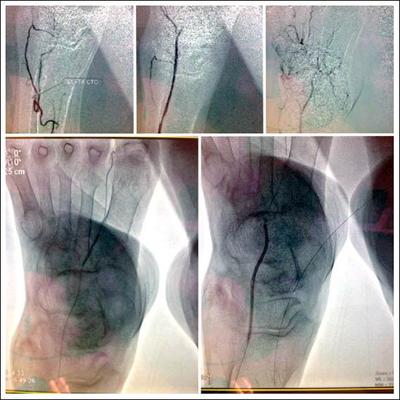

▲北港媽祖醫院心臟血管外科醫師陳偉華為人瑞阿嬤進行「氣球血管成型術」(下圖),保住阿嬤的腳不必截肢。(記者廖淑玲翻攝)

105歲的李姓阿嬤,因高齡,血管老化、鈣化,右腳嚴重病變,且下肢肌肉逐漸變黑、變硬,不良於行,有截肢的威脅,去年底才就診,經陳偉華施行氣球血管成型術,利用一條約30至40公分導管,疏通已發生阻塞的血管後,再使用醫療用氣球撐開血管,讓血液得以通行,保住阿嬤的腳不必開刀截肢,目前阿嬤還能每天走路運動一個小時。